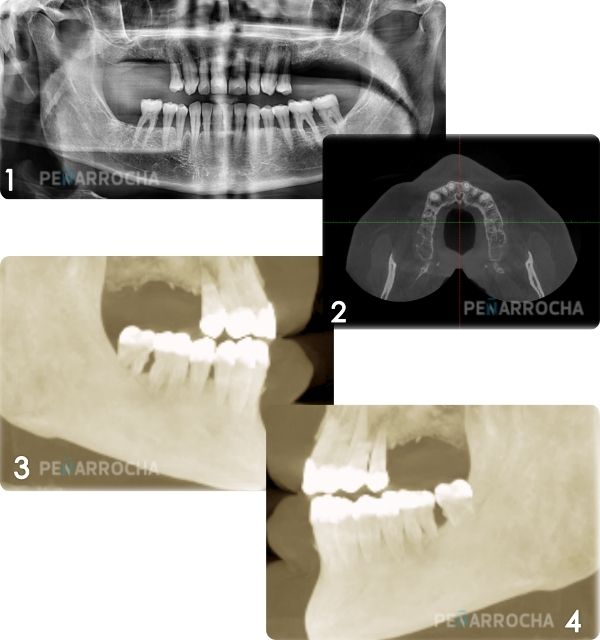

Realizamos un estudio completo mediante radiografías y tomografías 3D para determinar la calidad y cantidad de hueso disponible. Es importante evaluar si el paciente cumple con los requisitos necesarios para este tipo de implante.

Eduvigis Arnalda Benages llegó a nuestra clínica dental IDIM en 2016 buscando una solución definitiva para su problema dental. Sufría dolor constante y no podía comer debido a la movilidad de sus dientes. Su diagnóstico reveló una atrofia ósea severa tanto en el maxilar como en la mandíbula, provocada por infecciones periodontales y peri-implantarias.

Gracias a nuestro enfoque integral y el uso de técnicas avanzadas como los implantes de carga inmediata, logramos transformar su situación. Realizamos una planificación detallada con tomografía 3D, llevando a cabo procedimientos específicos para corregir la pérdida ósea y devolviendo funcionalidad y estética a su sonrisa.